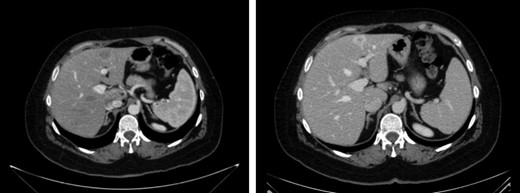

Paranasal sinuses CT showed a solid lesion located in middle, upper and common right meatus, ethmoid hemibody, with extension to lamina papyracea and lamina cribosa with superior oblique infiltration. (Fig. 1)

Ten months later, CT revealed two hepatic lesions (segment III of 3 cm and segment VII of 1 cm) (Fig. 2) The biopsy confirmed the original histology of SNUC. Chemotherapy with docetaxel 75 mg/m2, cisplatin 75 mg/m2 and 5 FU 750 mg/m2 every 3 weeks for 3 months was administrated. Because of minimal response was achieved after chemotherapy (Fig. 2) a non-anatomical metastasectomy was performed.

CT scan first relapse. Liver metastases: sIII and sVII 2.2 CT scan after neoadjuvant chemotherapy.